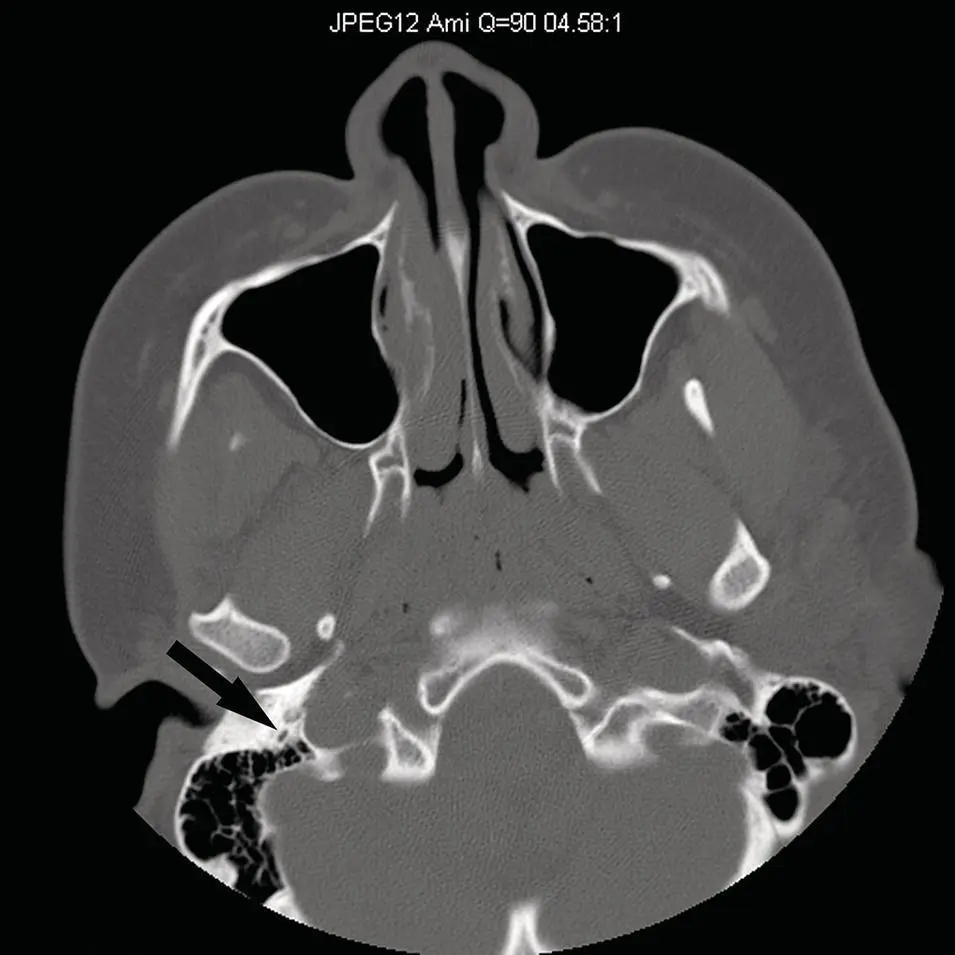

The Hounsfield unit (H) (named for Godfrey Hounsfield, inventor of the CT scanner) is the unit of density measurement for CT. These units are assigned based on the degree of attenuation of the X‐ray beam by tissue in a given voxel (volume ele ment) and are assigned relative to water (0H) ( Table 2.1). The scale ranges from −1024H for air, to +4000H for very dense bone. The images are created based on a gray scale from black (−1024 H) to white (+4000 H) and shades of gray. Despite the wide range of units, majority of tissues in the human body are between −100 and +100 H. Soft tissues and parenchymal organs are in a range between 20 and 80 H, whereas fat is approximately −100 H. Simple fluid is 0 H, but proteinaceous fluid can be upward of 25 H. Unclotted and clotted blood varies depending on the hemoglobin concentration and hematocrit but average measurements are 50 and 80 H, respectively. CT images are displayed using a combination of “window widths” (WW, range of CT numbers from black to white), and “window levels” (WL, position of the window on the scale), which are based on the attenuation characteristics of tissues. Typically, head and neck images are interpreted using “soft‐tissue windows” (WW 500 H, WL 30 H), “bone windows” (WW 2000, WL 500), or “lung windows” (WW 1500, WL 500). The “soft‐tissue windows” demonstrate the slight density differences of soft tissues, whereas “bone windows” demonstrated cortical and medullary features of bones with sharp detail. “Lung windows” demonstrate the sharp interface of air and the fine soft‐tissue components of lung parenchyma.

Although the density of the salivary glands is variable, the parotid glands tend to be slightly lower in density relative to muscle, secondary to a higher fat content and become progressively more fat replaced over time. The CT density of parotid glands varies from −10 to +30 H. The submandibular glands are denser than parotid glands and are equivalent in density to muscle. The submandibular glands vary in density from +30 to +60 H.